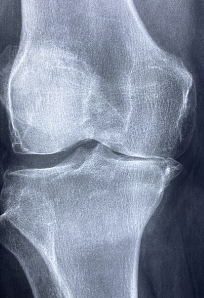

- 관절염 증상 완화: 연골의 변성을 막아 연골의 탄성을 유지하고, 뼈에 부착되어있는 연골 조직을 회복하여 관절의 마찰을 줄여 관절염으로 인한 통증을 완화할 수 있습니다.

- 뼈 건강 유지: 글루코사민은 뼈 조직을 구성하는데 필요한 성분 중 하나인 그리코사미노글리칸을 생성합니다. 이를 통해 뼈의 건강을 유지하고, 뼈 밀도를 높일 수 있습니다.

- 손상된 연골 조직 회복: 글루코사민은 손상된 연골 조직을 회복하는데 도움을 줄 수 있습니다.